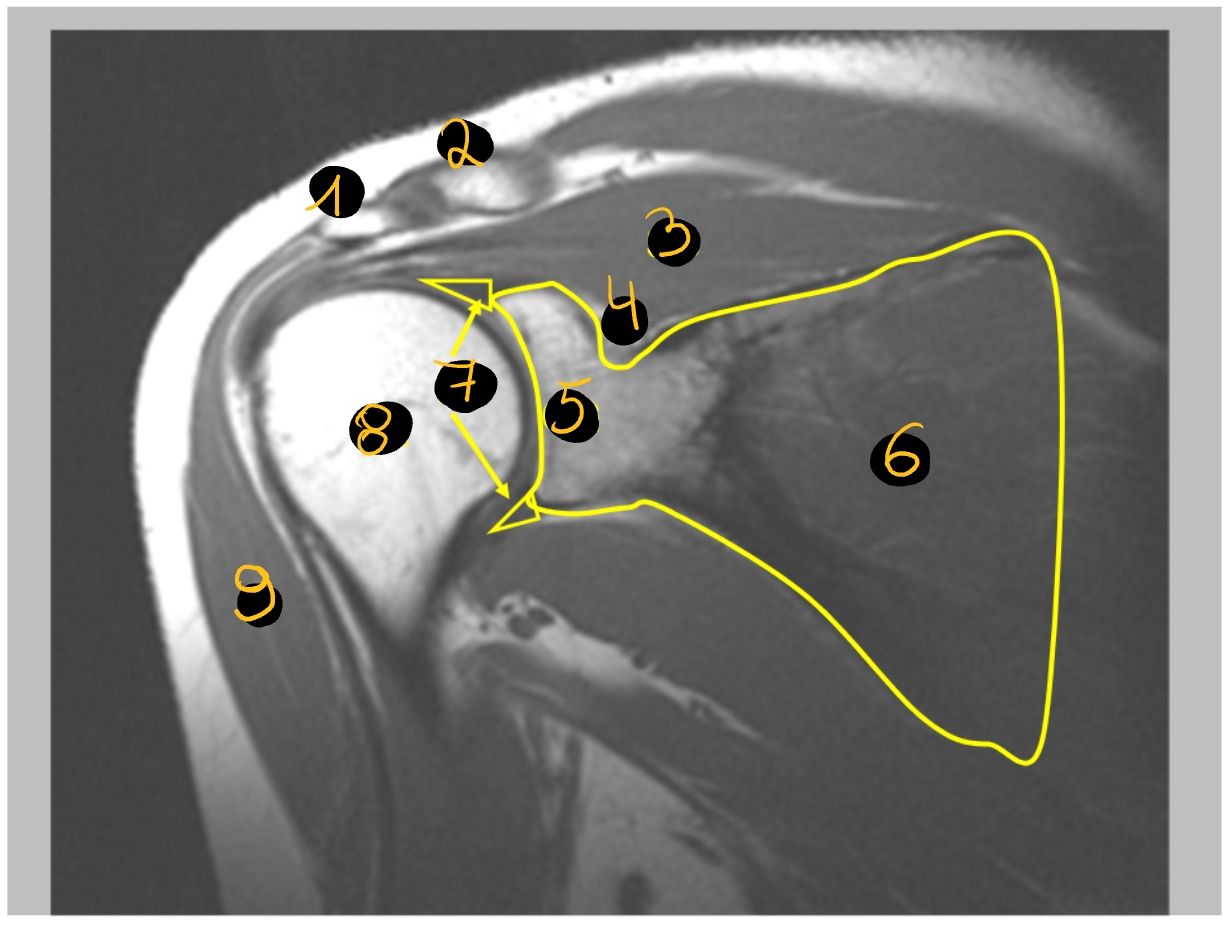

acromion

clavicula

m. supraspinatus

hecht aan op tuberculum majus

incisura scapulae

daarin ligt de nervus suprascapularis

cavitas glenoidalis

scapula

labrum glenoidale

vezelige structuur die de gewrichtspan doet vergroten

caput humeri

m. deltoideus

MRI → toont botten, spieren & pezen

→ rechter schouder (MR): coronale doorsnede